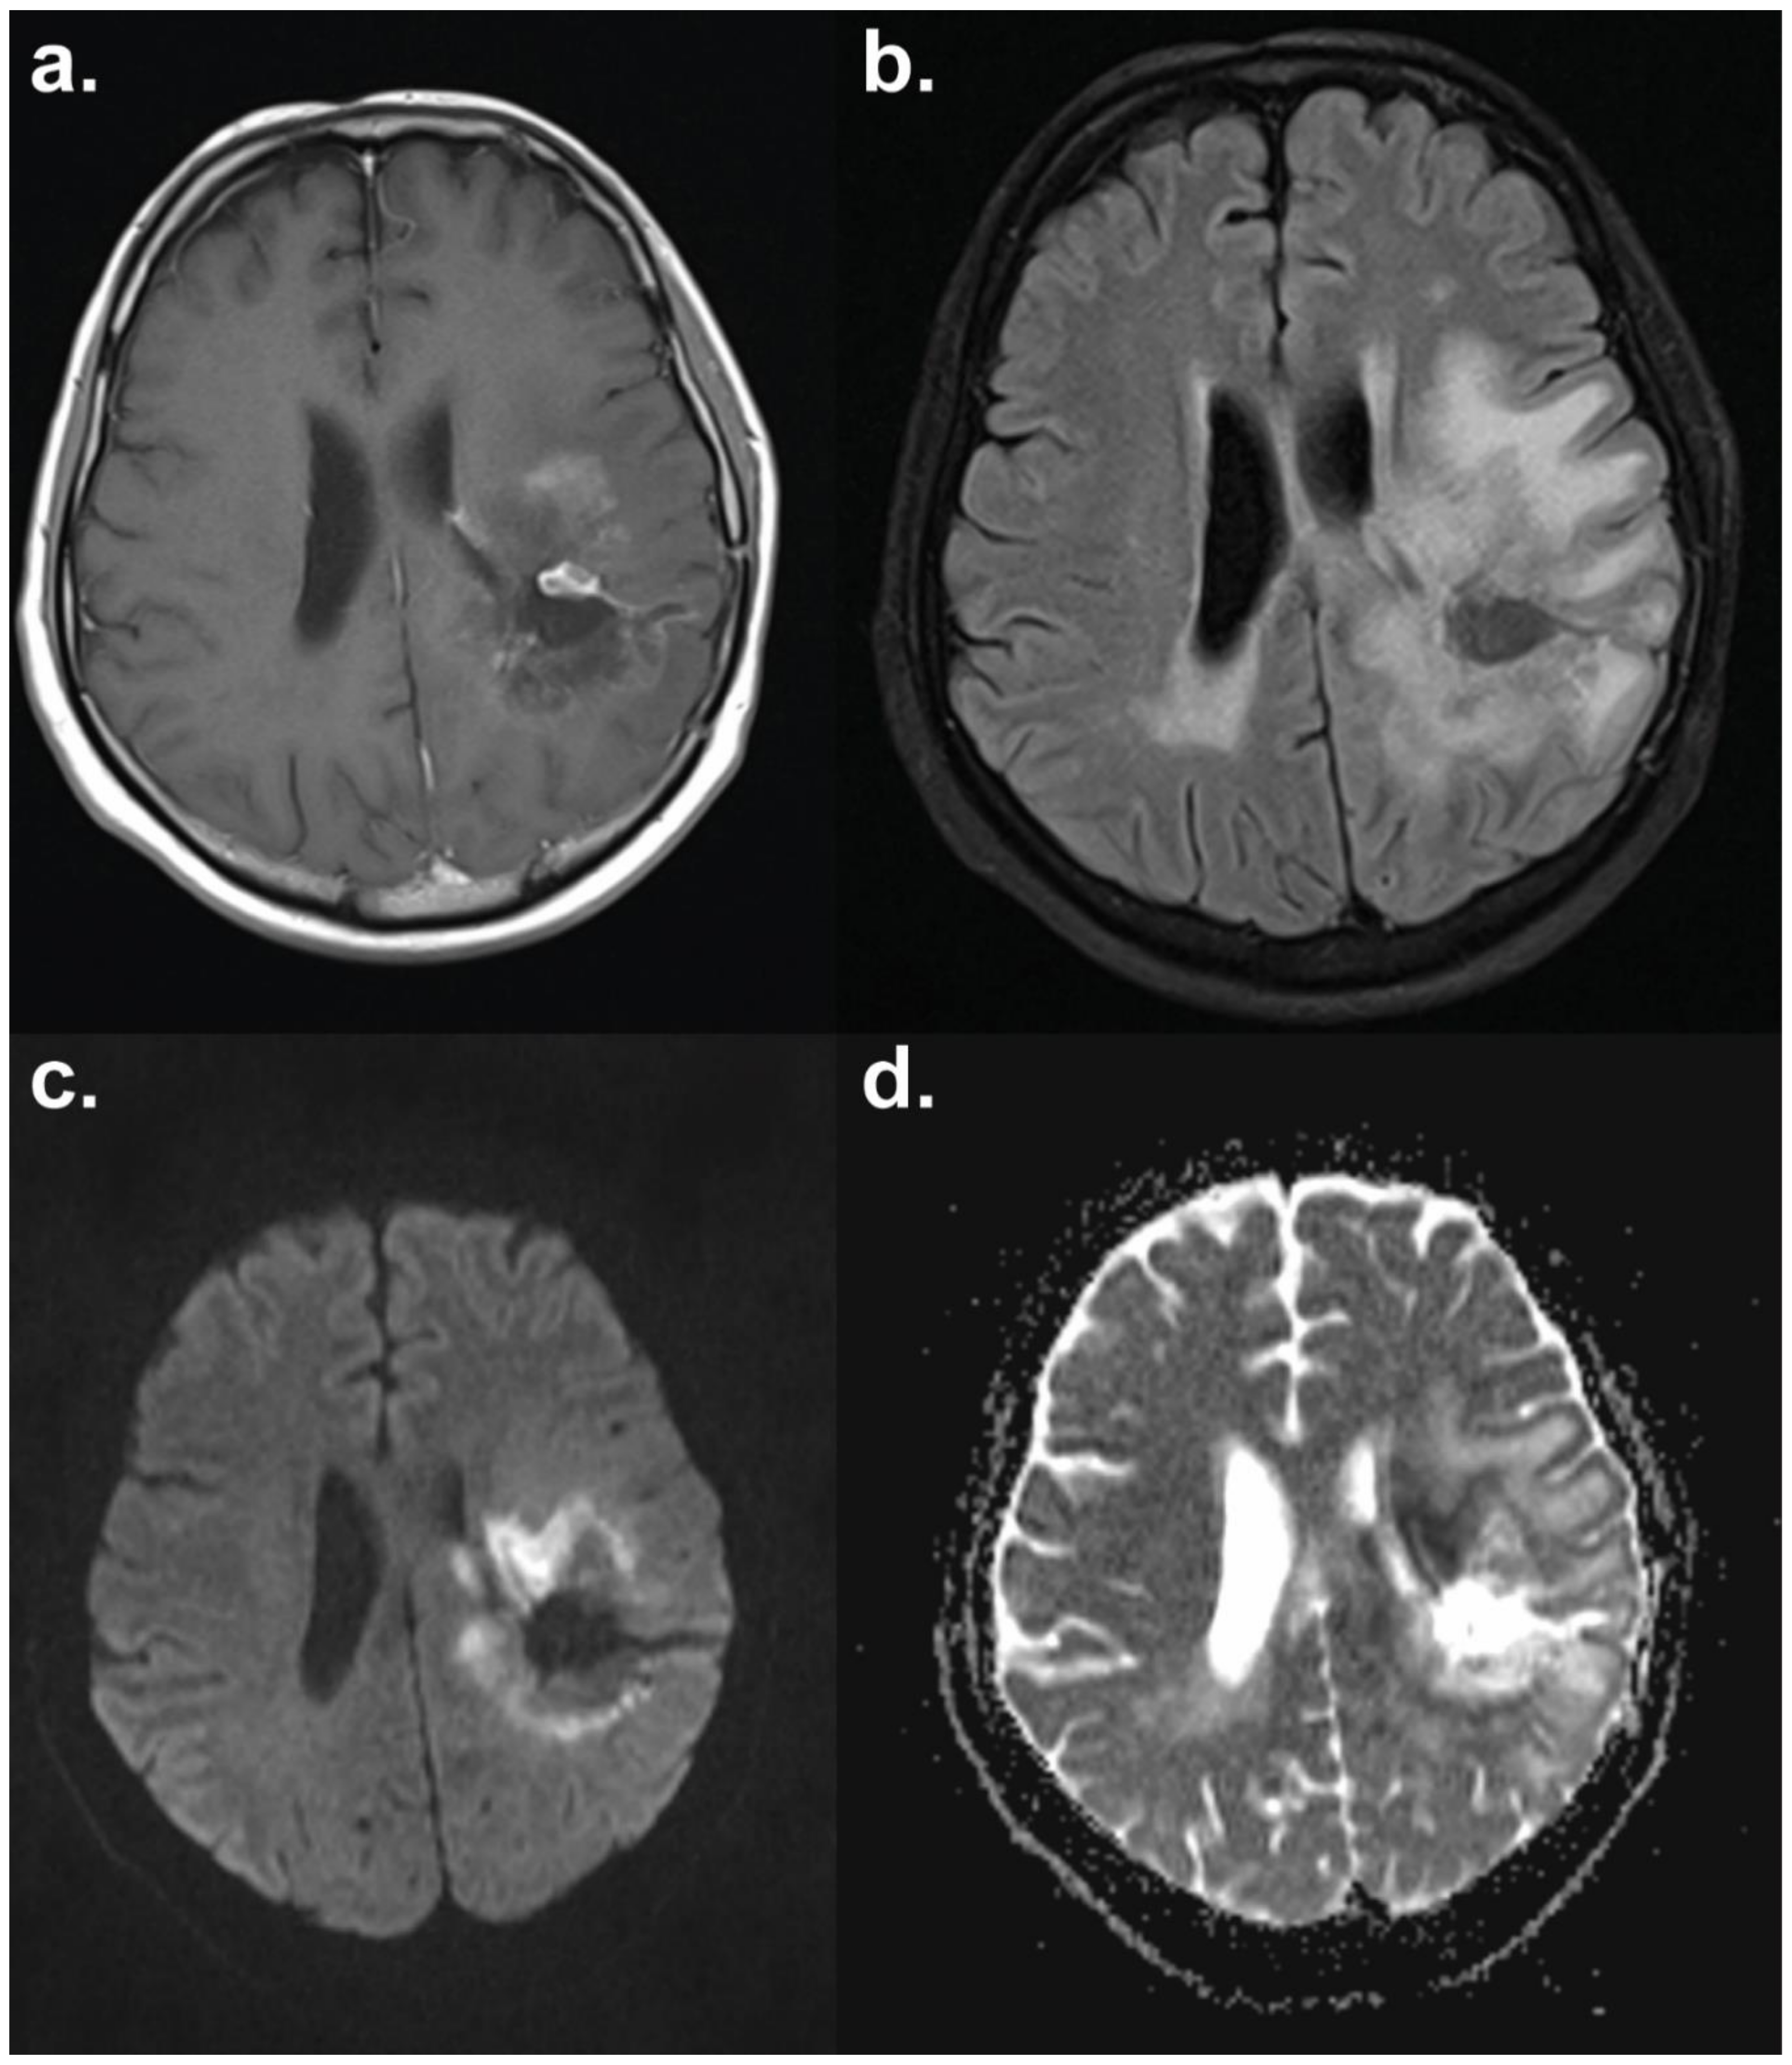

6.1. Diffusion-Weighted MRI

- Chu, H.H.; Choi, S.H.; Ryoo, I.; Kim, S.C.; Yeom, J.A.; Shin, H.; Jung, S.C.; Lee, A.L.; Yoon, T.J.; Kim, T.M.; et al. Differentiation of true progression from pseudoprogression in glioblastoma treated with radiation therapy and concomitant temozolomide: Comparison study of standard and high-b-value diffusion-weighted imaging. Radiology 2013, 269, 831–840. [Google Scholar] [CrossRef]

- Kim, J.Y.; Park, J.E.; Jo, Y.; Shim, W.H.; Nam, S.J.; Kim, J.H.; Yoo, R.E.; Choi, S.H.; Kim, H.S. Incorporating diffusion- and perfusion-weighted MRI into a radiomics model improves diagnostic performance for pseudoprogression in glioblastoma patients. Neuro-Oncology 2018. [Google Scholar] [CrossRef]

- Hein, P.A.; Eskey, C.J.; Dunn, J.F.; Hug, E.B. Diffusion-weighted imaging in the follow-up of treated high-grade gliomas: Tumor recurrence versus radiation injury. Am. J. Neuroradiol. 2004, 25, 201–209. [Google Scholar] [PubMed]

- Asao, C.; Korogi, Y.; Kitajima, M.; Hirai, T.; Baba, Y.; Makino, K.; Kochi, M.; Morishita, S.; Yamashita, Y. Diffusion-weighted imaging of radiation-induced brain injury for differentiation from tumor recurrence. Am. J. Neuroradiol. 2005, 26, 1455–1460. [Google Scholar] [PubMed]

- Zeng, Q.S.; Li, C.F.; Liu, H.; Zhen, J.H.; Feng, D.C. Distinction between recurrent glioma and radiation injury using magnetic resonance spectroscopy in combination with diffusion-weighted imaging. Int. J. Radiat. Oncol. Biol. Phys. 2007, 68, 151–158. [Google Scholar] [CrossRef] [PubMed]